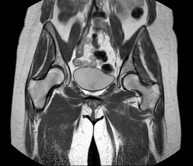

Exploración para el estudio de lesiones en tendones, ligamentos y pequeñas articulaciones. Es la prueba que mejor permite diagnosticar las frecuentes capsulitis por traumatismo, la artrosis y las roturas de tendones. Tiene una duración aproximada de 20 minutos. No emplea radiación ionizante. - RM Caderas

Exploración para el estudio de lesiones en tendones, músculos y articulaciones coxofemorales. Permite identificar de forma precoz la artrosis de cadera. Resulta muy útil para detectar las bursitis y la osteopatía dinámica del pubis, frecuente en deportistas. Tiene una duración aproximada de 20 minutos. No emplea radiación ionizante. - RM Sacroilíacas